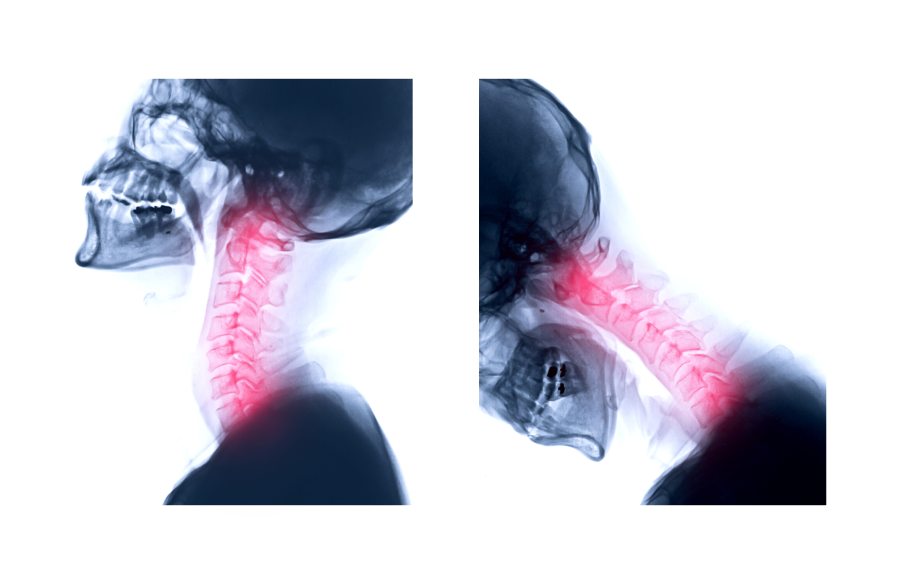

L’occlusion dentaire, c’est-à-dire la manière dont les dents s’emboîtent, joue un rôle central dans la stabilité de la tête et du cou. Une occlusion déséquilibrée peut entraîner une asymétrie musculaire. Cela se traduit souvent par une inclinaison de la tête, des tensions cervicales ou des adaptations posturales.

Le chirurgien-dentiste réalise un examen clinique complet, avec évaluation de l’occlusion, de la position mandibulaire, des fonctions orales (respiration, déglutition, phonation) et de la posture statique. Des photographies et des radios peuvent être réalisées pour affiner le diagnostic.